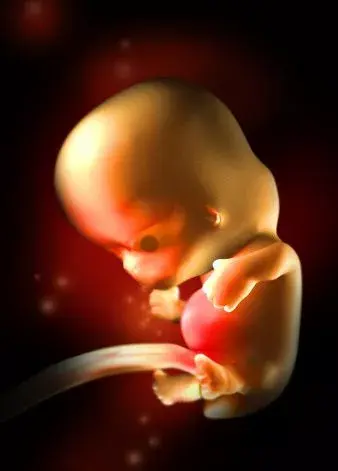

8周:

胎兒長到1.66厘米,胎形已定,可分出胎頭、體及四肢,胎頭大于軀干。B超可見胎囊約占官腔1/2,胎兒形態及胎動清楚可見,并可看見卵黃囊。器官已有明顯的特征,手指和腳趾間有少量的蹼狀物。胚胎的各種復雜的器官都開始成長,牙和腭開始發育,耳朵在繼續成形,胎兒的皮膚很薄,血管清晰可見。胚胎開始有運動。

9周:

胎兒長到2.15厘米,胎兒頭大于胎體,各部表現更清晰,頭顱開始鈣化、胎盤開始發育。B超可見胎囊幾乎占滿宮腔,胎兒輪廓更清晰,胎盤開始出現。胎兒所有的器官、肌肉、神經都開始工作,并且發育迅速。手部從手腕開始變得稍微有些彎曲,雙腳開始擺脫蹼狀的外表,眼簾開始覆蓋住眼睛。